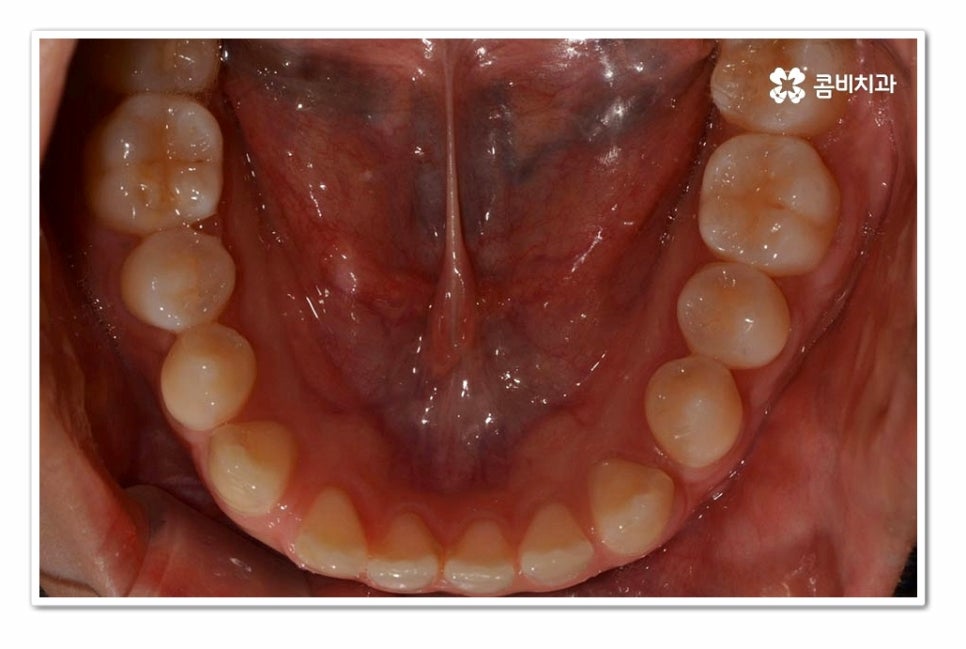

위 환자분의 경우 윗니 만이 아니라 아랫니도 벌어져 있기 때문에

라미네이트와 같이 단기적으로 심미성을 고려한 치료보다는

치아교정을 통해 치아의 건강부터 교합, 심미성을 함께

개선할 수 있는 치료 계획을 세운 것이라 할 수 있어요.